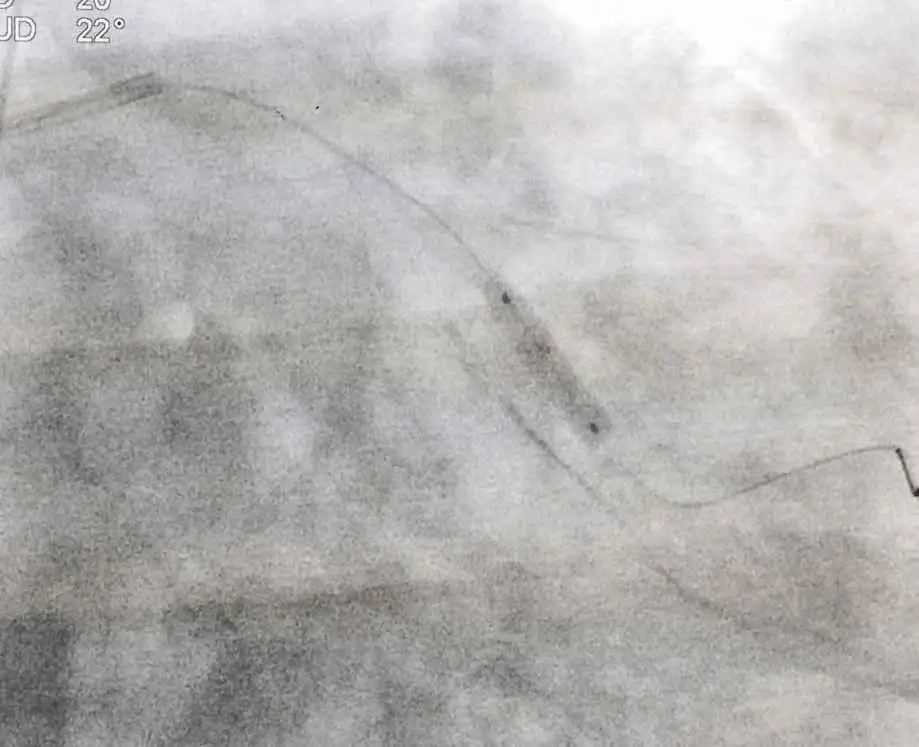

A small wire (0.14”) is advanced through the clot blocking the artery. A balloon and thrombectomy device (designed to suck clot out of the blood vessel) is passed over the wire and down the vessel. The thrombus is removed from the vessel. The following image shows the device and the amount of clot that could be removed from the vessel.

The patient reports a big improvement in his pain shortly after the balloon is deflated. In fact, his pain is almost gone. A stent is placed at the site of the occlusion and final angiography is performed.